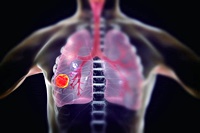

CT 스캔은 폐 손상의 정도를 평가하는 데 유용한 검사입니다. 특히 폐포 파괴가 특징인 폐기종을 감지하는 데 유용합니다. CT 스캔은 폐 손상의 위치와 정도를 정확히 파악하여 치료 결정을 도울 수 있습니다.

만성 폐쇄성 폐질환의 증상을 조기에 인식하고 신속하게 진단받는 것은 이 만성 폐질환을 관리하는 데 매우 중요합니다. 만성 기침, 숨 가쁨 등의 증상에서부터 폐활량 측정과 CT 스캔 같은 진단 방법까지, 증상과 진단 방법을 이해함으로써 적절한 치료를 받을 수 있습니다. 의료 제공자와 협력하여 만성 폐쇄성 폐질환을 효과적으로 관리하고 삶의 질을 향상시킬 수 있습니다.